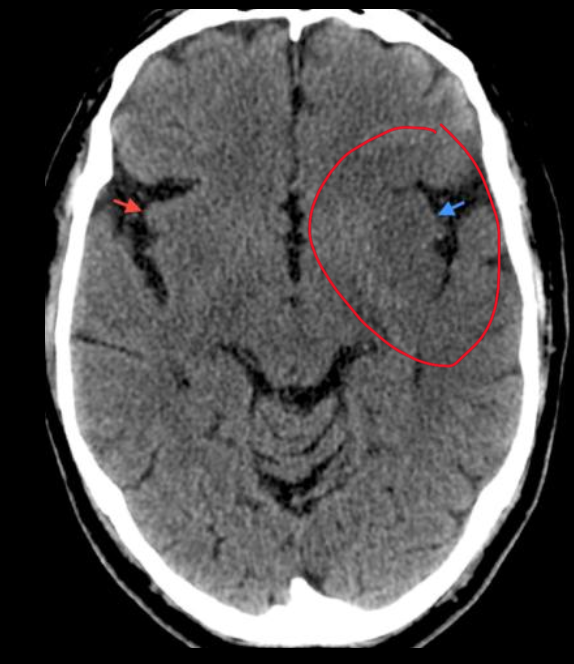

23

Q

A

EVC hemorragico

HSA